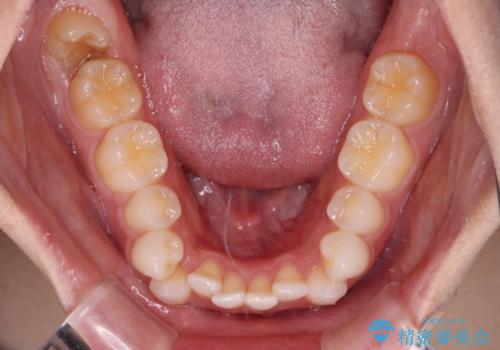

- 前歯のデコボコとクロスバイトを気にして来院された患者様です。

上下ともにデコボコはそれほど強くありませんでしたが、非抜歯では口元が突出した仕上がりとなる可能性があるため、上下左右の第一小臼歯4本を抜歯し、ワイヤー装置での抜歯矯正を行うこととしました